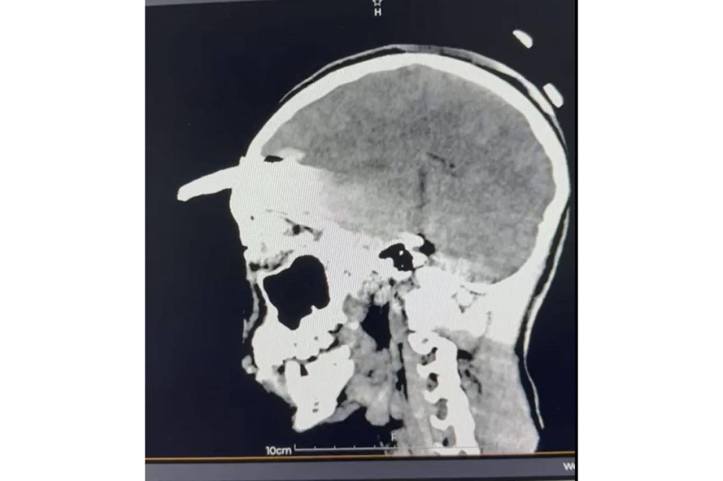

Tras confirmarse un traumatismo craneoencefálico severo, se realizaron estudios inmediatos que determinaron la profundidad y ubicación del objeto. Ante la complejidad del caso, el neurocirujano Elías Sinahí Ramírez Sánchez determinó que el adolescente debía ser trasladado a la T-1, que cuenta con el equipo necesario para una intervención especializada.

Los estudios de imagen permitieron ubicar con precisión el objeto, mientras el menor recibía tratamiento con antibióticos de amplio espectro para prevenir infecciones asociadas con el instrumento metálico.

Después de un análisis minucioso y una planeación quirúrgica, el doctor Ornelas González dirigió un procedimiento de cuatro horas que permitió retirar exitosamente la coa sin afectar tejido cerebral, en una intervención que confirmó la pericia y capacidad del equipo médico.